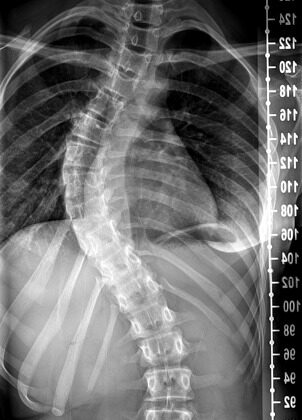

اعوجاج العمود الفقري هو انحناء جانبي غير طبيعي في العمود الفقري، بحيث يظهر العمود الفقري بشكل حرف (S) أو حرف (C) بدلًا من أن يكون مستقيمًا من الأعلى إلى الأسفل.

من الطبيعي أن يكون للعمود الفقري انحناءات بسيطة للأمام والخلف تساعد الجسم على التوازن والحركة، لكن في حالة الاعوجاج، يكون الانحناء جانبيًا وغير متوازن.

كيف يتم تشخيص اعوجاج العمود الفقري؟

يبدأ التشخيص عادة بفحص بسيط في العيادة، يقوم فيه الطبيب بطلب من الطفل أن ينحني للأمام، وهي طريقة تُعرف باسم اختبار الانحناء الأمامي (Adam’s test).

خلال هذا الاختبار، يمكن للطبيب أن يلاحظ أي انحناء غير طبيعي في الظهر أو عدم تساوي في الجانبين.

إذا لاحظ الطبيب علامات واضحة، يطلب أشعة سينية (X-ray) على العمود الفقري لتحديد:

درجة الانحناء (باستخدام زاوية كوب Cobb angle).

مكان الاعوجاج (في الظهر العلوي، أو السفلي، أو كليهما).

ما إذا كان في اتجاه اليمين أو اليسار.

كيف يُقاس اعوجاج العمود الفقري؟

يقوم الطبيب أو أخصائي العلاج الطبيعي بقياس درجة انحناء العمود الفقري بوحدة الدرجات. ويتم تحديد شدة الانحناء بناءً على درجة الانحناء كالآتي:

لا يوجد اعوجاج: أقل من 10 درجات.

اعوجاج بسيط: بين 10 و24 درجة.

اعوجاج متوسط: بين 25 و39 درجة.

اعوجاج شديد: أكثر من 40 درجة.

يمكن تشبيه هذا بقياس الزوايا في درس الهندسة باستخدام المنقلة. يستخدم الطبيب جهازًا يُسمّى سكوليميتر ليقيس الانحناء بوضعه على ظهر المريض. وفي بعض الحالات، قد يطلب الطبيب أشعة سينية للظهر لتحديد درجة الانحناء بدقة أكبر.